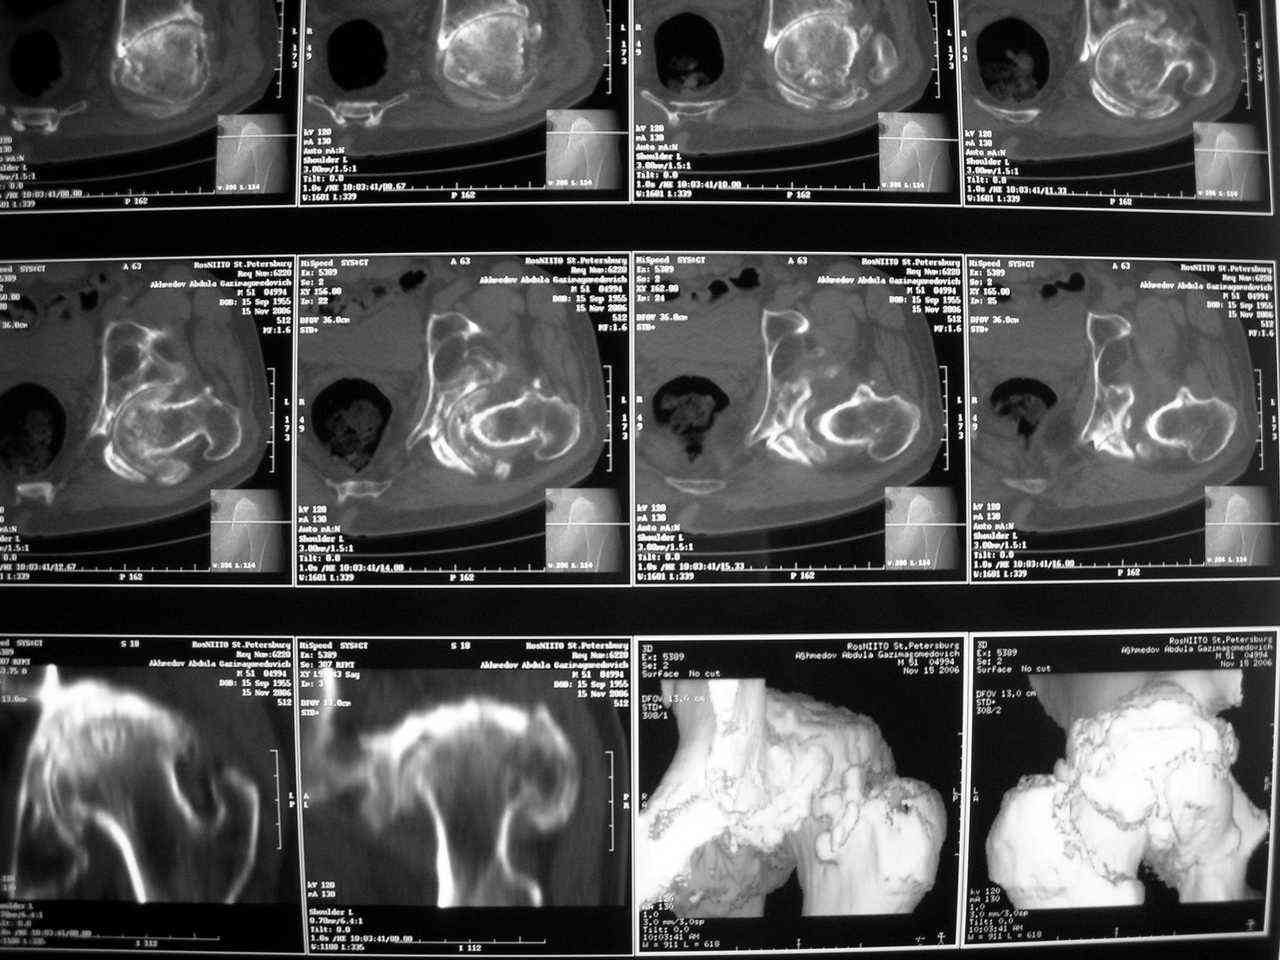

Еще одно наблюдение, неправильно сросшийся перелом заднего отдела ВВ с ввихом головки бедра 16-и летней давности.

С уважением, Р.Тихилов